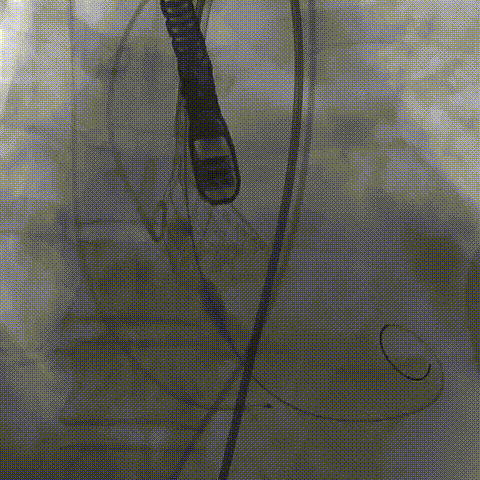

瓣膜(AV29)完全回收后重新定位释放

瓣膜(AV29)工作位正交体位造影位置良好,左冠显影正常